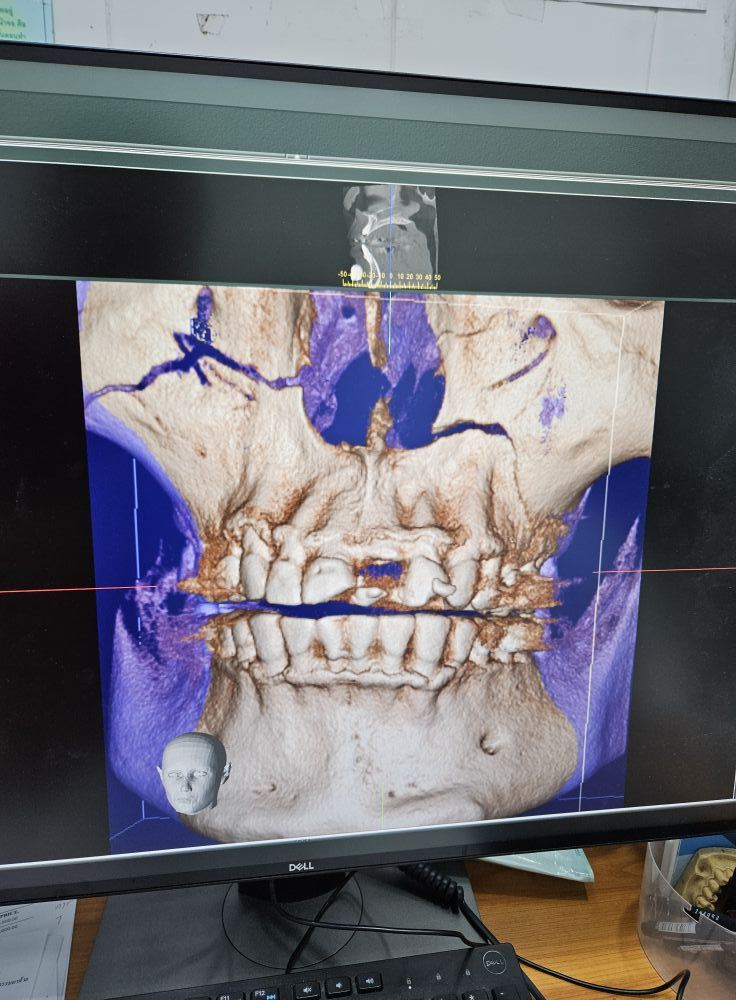

วูบครั้งนี้ถึงขั้นเจ็บหนัก ต้องไปนอนโรงพยาบาลอยู่ 4 คืน เพราะกะโหลกหน้าแตก ฟันหักไป 3 ซี่ กรามหัก และต้องเย็บเพดานปากด้านในอีก 16 เข็ม ต้องกินแต่อาหารเหลวอยู่เดือนครึ่งผ่านหลอดดูด เพราะต้องยึดฟันบนกับล่างให้ติดกันด้วยลวดเหล็กจนพูดไม่ถนัด-อ้าปากไม่ได้จนถึงวันนี้ ทำให้ต้องงดงานบรรยายและนัดหมายอื่น ๆ ทั้งหมดในช่วง 2 เดือนที่ผ่านมา ซึ่งต้นกุมภาพันธ์นี้น่าจะหายดี